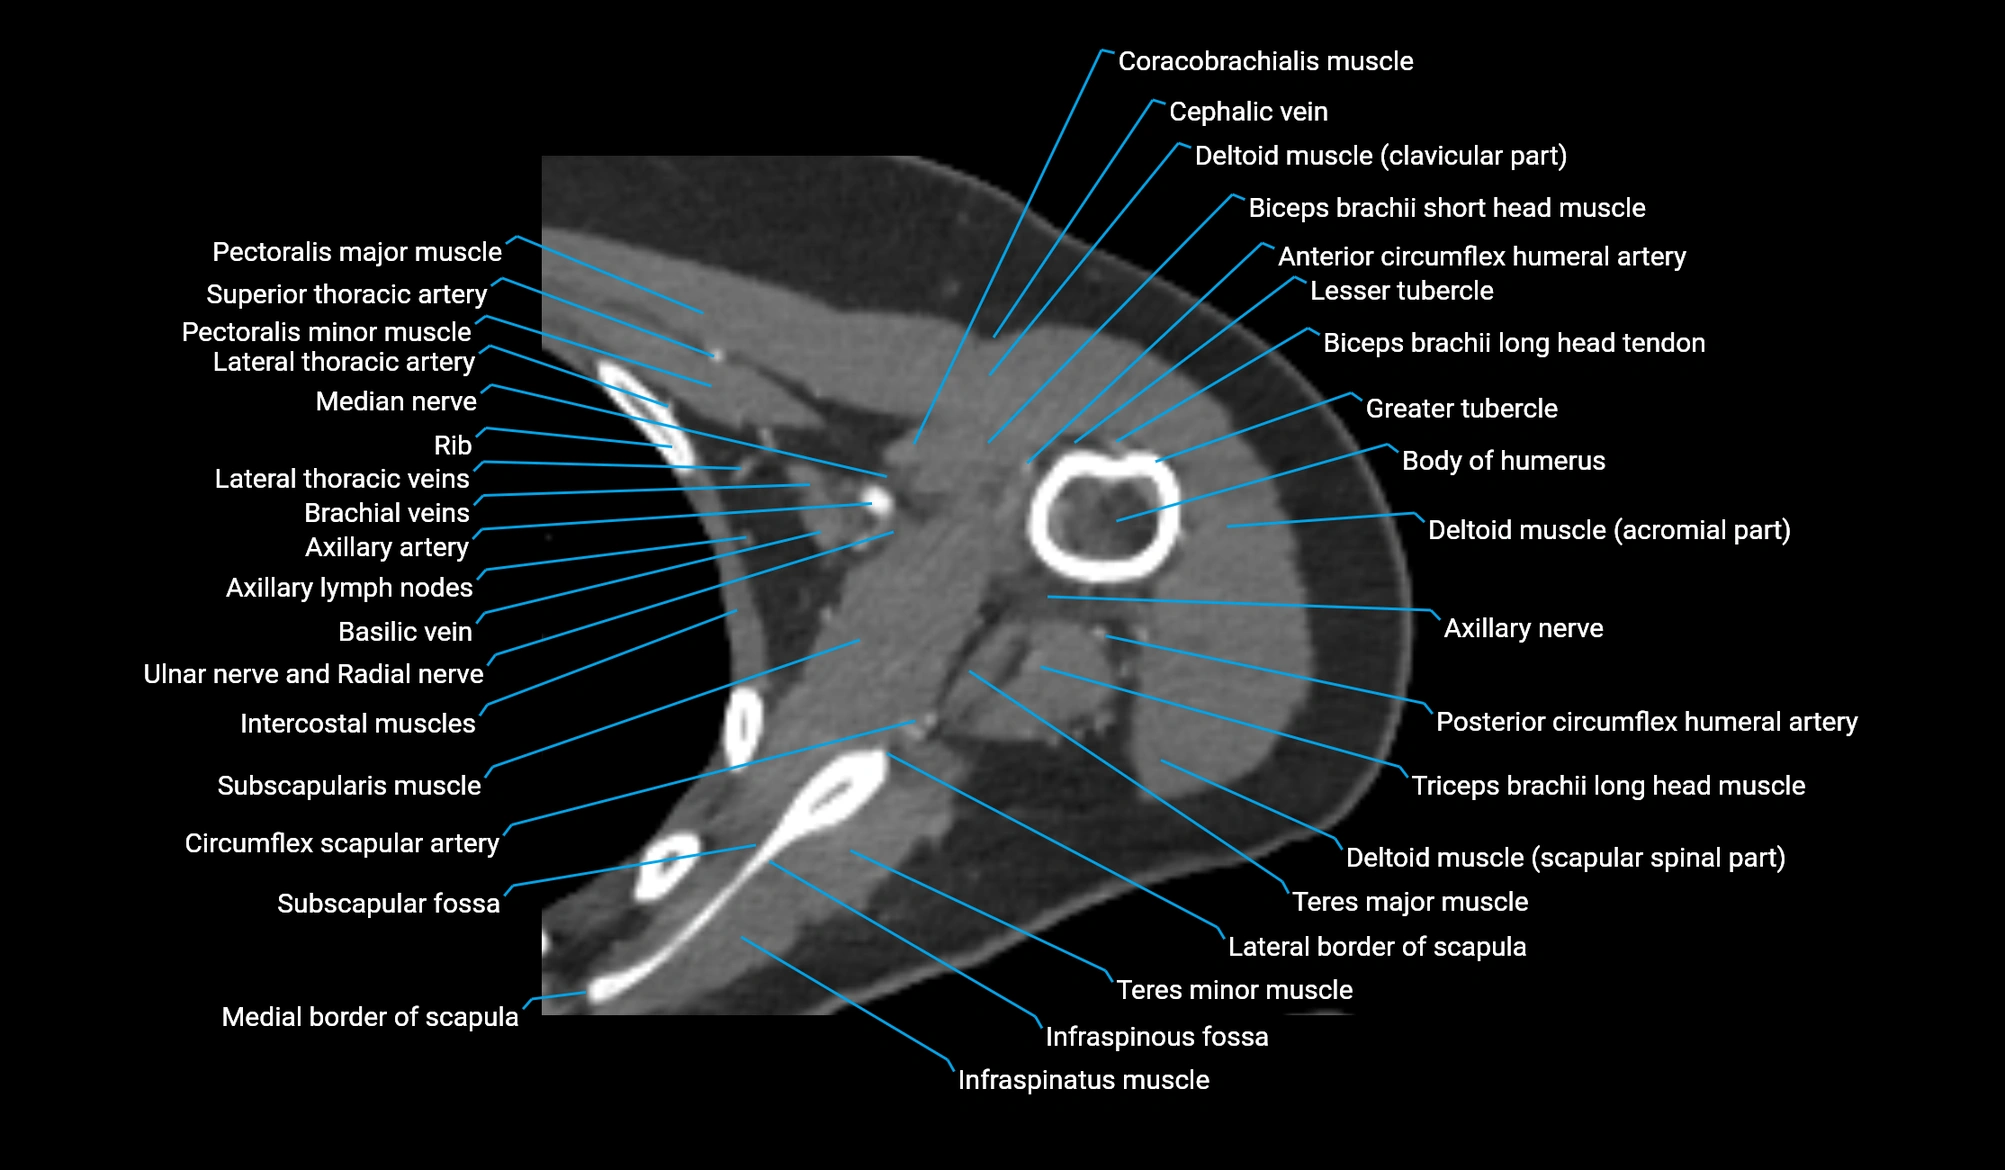

- Head of humerus

- Greater tubercle of humerus

- Lesser tubercle of humerus

- Glenoid labrum

- Posterior circumflex humeral artery

- Axillary nerve

- Subscapularis muscle

- Infraspinatus muscle

- Teres minor muscle

- Teres major muscle

- Coracobrachialis muscle

- Cephalic vein

- Clavicular part of deltoid muscle

- Scapular spinal part of deltoid muscle

- Lateral border of scapula

- Medial border of scapula

- Subscapular fossa

- Pectoralis major muscle

- Pectoralis minor muscle

- Circumflex scapular artery